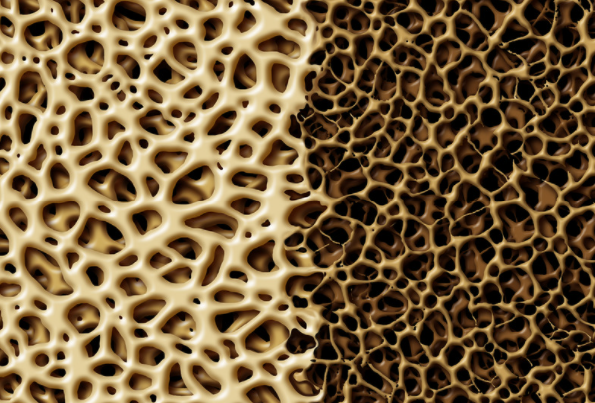

In the last decade our understanding of tendinopathy has continued to involve. Tendinopathy is often classified as reactive or degenerative. Reactive tendinopathy sees a non inflammatory increase in cell activity, which leads to a resultant increase in water in the tendon. Typically patients will present with an acute exacerbation of symptoms that cn be related to an increase or change in activity. Other causes could include a change in footwear, sporting equipment, or work duties.

Degenerative Tendinopathy sees areas of collagen breakdown, reduced tenocytes (cells), and vascular and nerve ingrowth. Degenerative tendinopathy is more likely to be present in people who have had repeated episodes of symptoms over time. Whilst degenerative areas have little capacity to change, strengthening the surrounding tendon leads to improvements. Symptoms may take a few weeks to settle, and rehabilitation can take a minimum of 3-6 months.

Studies have shown patients can have symptoms of pain but no pathology on imaging. Conversely degeneration can be present in the absence of pain. Rehabilitation therefore focusses on treating symptoms and functional deficits, rather than being based on the ultrasound or MRI report.